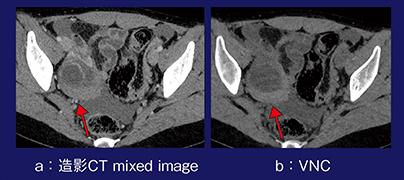

症例2は,30歳,女性,同じく右下腹部痛の症例である。造影CTで認められる高吸収域は,造影された腫瘍であるかどうかがはっきりしないが,仮想単純画像でもやはり高吸収であり,腫瘍ではなく卵巣出血であると判断できた(図2)。

図2 症例2:仮想単純画像による卵巣出血の描出